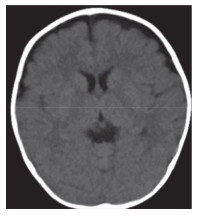

入院第2天(病程第6天)患儿双足及肛周出现散在红色斑疹。入院第7天双手、双足出现多处指甲与皮肤移行处脱皮,符合典型川崎病的诊断标准。分别于病程2~4 d(外院)和7~8 d进行2个疗程的丙种球蛋白(2 g/kg)治疗,发热无好转,外周血白细胞(19.06~24.80)×109/L;2次应用丙种球蛋白后C反应蛋白均出现一过性下降:第1次从 > 210.0 mg/L降至69.6 mg/L,第2次从56.3 mg/L降至28.0 mg/L,但3 d内再次升高至75.7 mg/L。铁蛋白7 d内逐步降至正常。入院第8天诊断为丙种球蛋白不反应型川崎病,加用静脉糖皮质激素[2 mg/(kg·d),共7 d],用药当日体温平稳,之后未再发热,外周血白细胞及C反应蛋白在使用激素后1周内逐步降至正常。入院第10天,头部MRI检查结果显示双侧额颞部硬膜下积液(图 3)。复查腰椎穿刺,脑脊液压力13 cmH2O。脑脊液常规检查:白细胞10×106/L,中性粒细胞百分比50%,单个核细胞50%。脑脊液生化检查:血糖3.93 mmol/L,蛋白1.14 g/L。1周后复查头部CT显示硬膜下积液无明显改变(图 4)。

| 图 3 患儿入院第10天头部MRI |